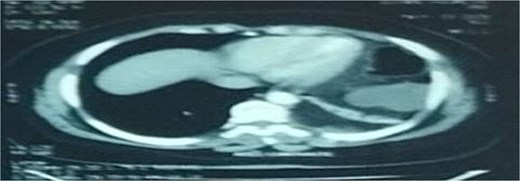

A 29-year-old female, with a history of cesarean section performed three months prior and no history of thoracoabdominal trauma, was admitted to the emergency department for an occlusive syndrome characterized by complete cessation of bowel movements and flatus, associated with vomiting, without other digestive or respiratory symptoms. On examination, the patient was conscious, haemodynamically and respiratorily stable. Abdominal examination revealed marked distension with epigastric tenderness, and digital rectal examination demonstrated an empty rectal ampulla. An initial plain abdominal radiograph, performed in the standing position and focused on the diaphragmatic domes, demonstrated colonic and small bowel distension with multiple air–fluid levels (Fig. 1). Subsequently, a thoraco-abdominopelvic CT angiography was performed, revealing a 3 cm left colonic herniation into the thoracic cavity through a partial posterolateral diaphragmatic rupture, associated with moderate left-sided pleural effusion (Figs 2–4). The herniation caused colonic stenosis at the diaphragmatic defect, with upstream distension of small bowel loops, the stomach remaining in its anatomical position (Fig. 5). These findings were consistent with acute intestinal obstruction secondary to a left-sided diaphragmatic hernia. Surgical management consisted of reduction of the herniated contents, assessment of their viability, and closure of the diaphragmatic defect using interrupted nylon sutures (sizes 2/0 and 0) (Fig. 6). Double drainage was instituted: a 28 Fr posteroinferior thoracic drain inserted through a dependent incision in the 5th intercostal space, and a Jackson–Pratt abdominal drain placed in the rectouterine pouch (Douglas’ pouch).

Axial section of an abdominal-pelvic CT scan showing a strangulated Bochdalek hernia with colonic and omental contents.